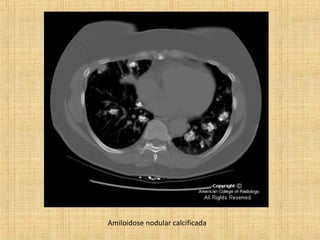

As principais informações do documento são: 1. Discute os padrões de doença pulmonar causados por metástases, incluindo nódulos, espessamento intersticial e obstrução das vias aéreas. 2. A prevalência de metástases pulmonares varia de 30-55% dependendo do tumor primário, e são mais comuns em pacientes acima de 50 anos. 3. Os achados clínicos mais comuns são dispneia, hemoptise e febre, enquanto exames de escarro ou lavado brô